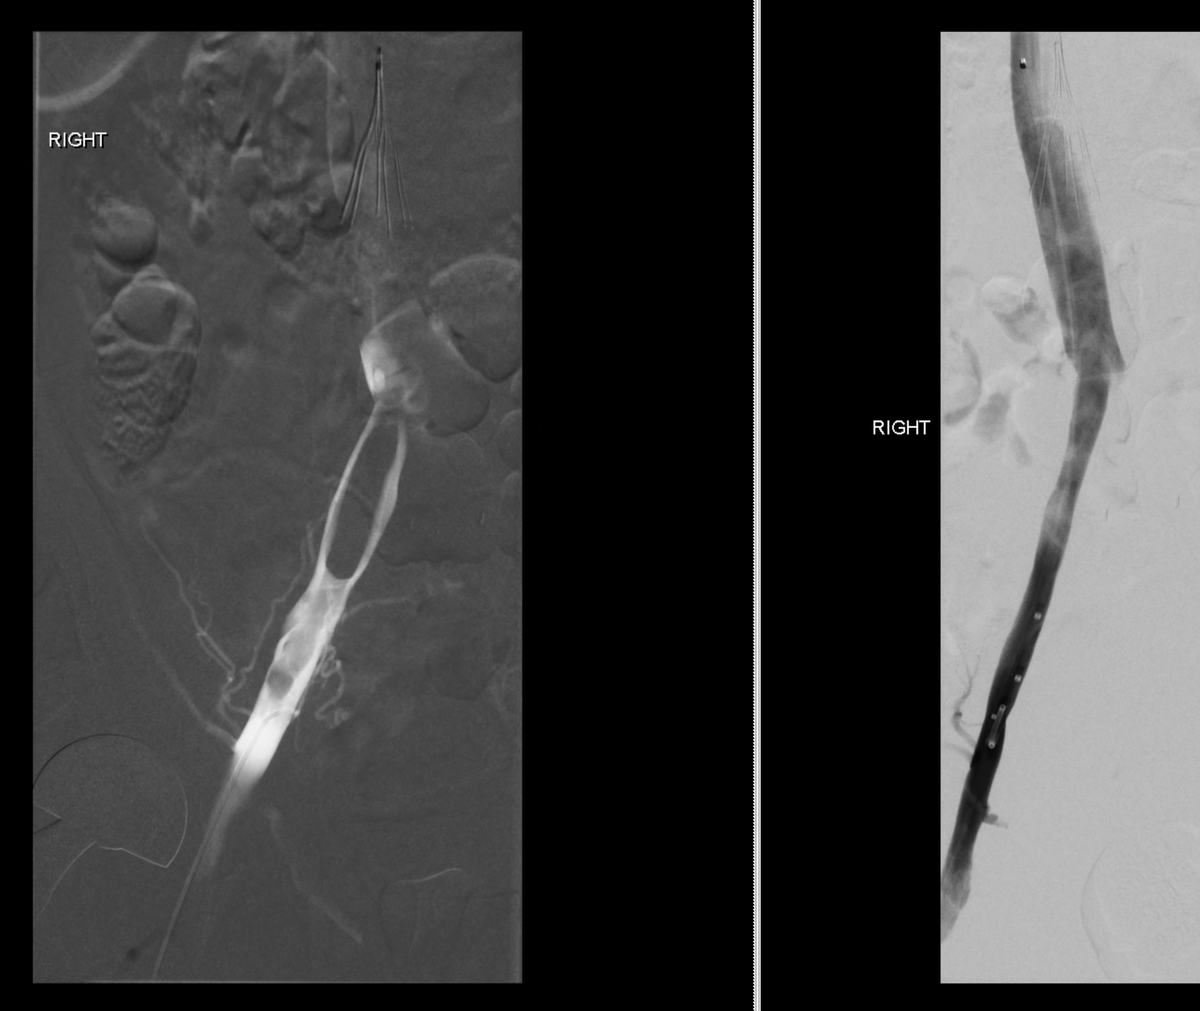

This patient presented with severe leg edema, iliocaval thrombus with 12 year old #IVCfilter. After a night of lysis a large vol of chronic appearing clot persisted. Was able to get most of it out with a few passes with the Inari T20 from popliteal access. #iRad